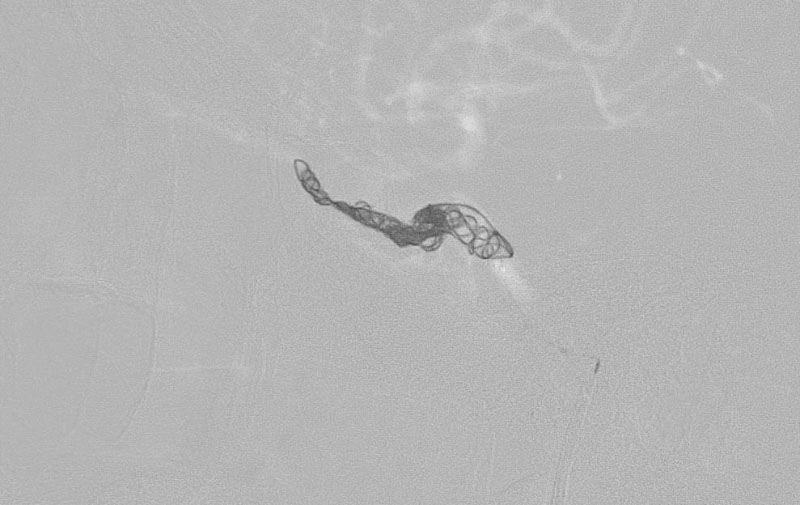

No.1190 手術中